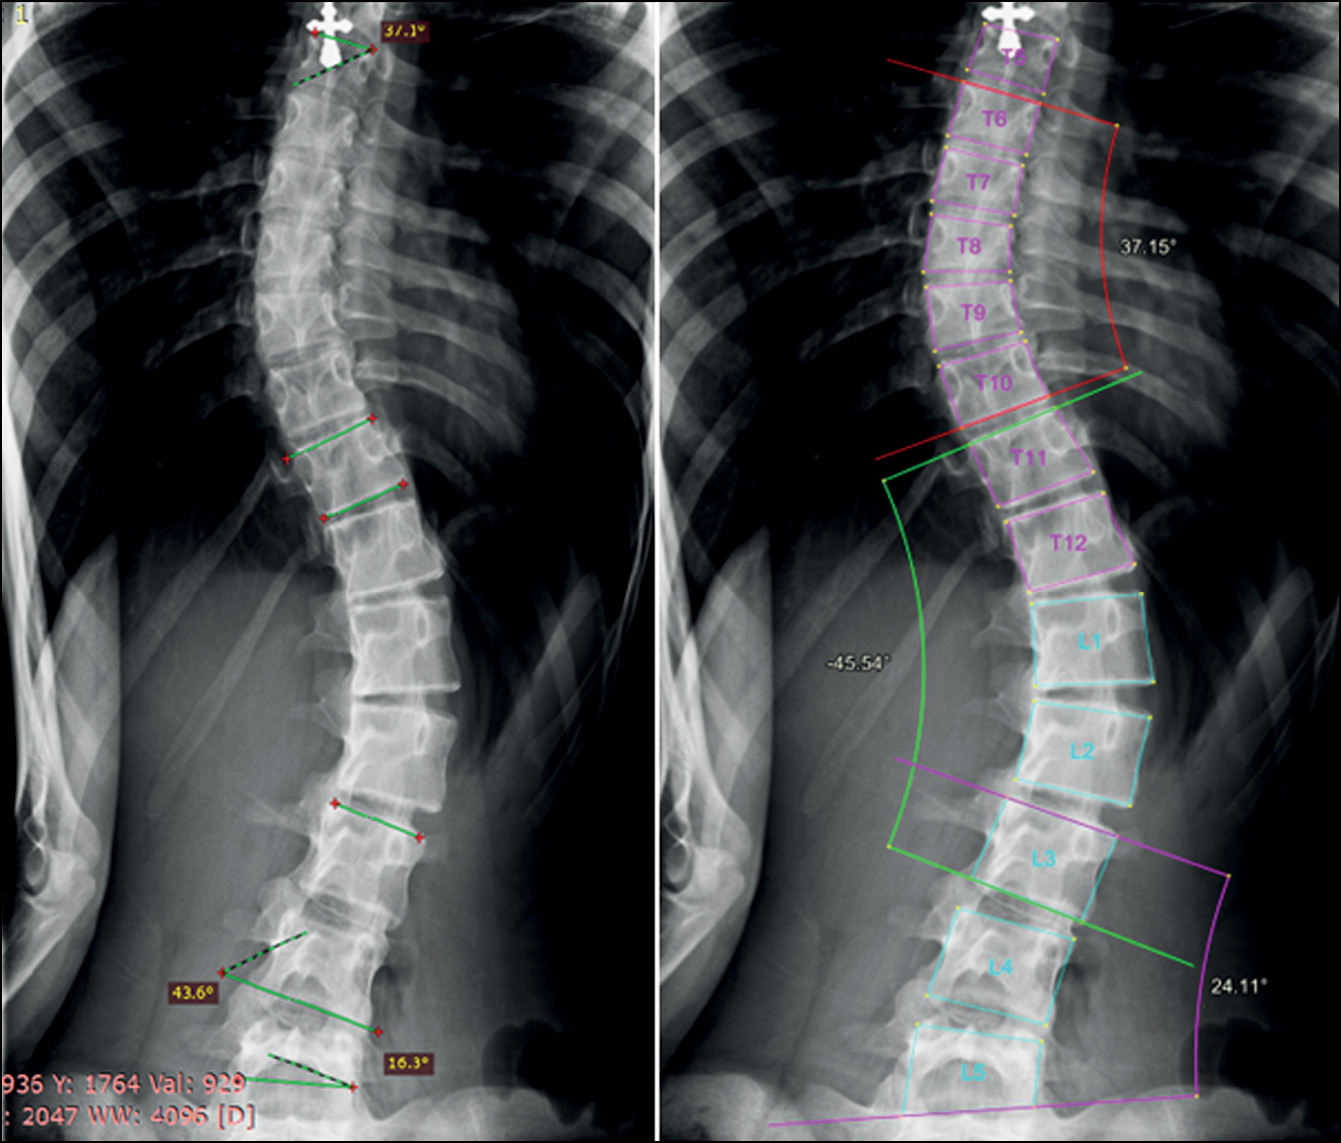

In some cases, the accuracy of the system in diagnosing grade III or IV scoliosis was not affected by significant measurement variability of Cobb’s angle between the system and the radiologist. Usually, these errors had been mainly found when assessing a nonprimary (secondary) curvature (Fig. 10).

Fig. 10. Grade 3 scoliosis diagnosed by the radiologist (left) and the AI system (right). Significant variability in measuring the lumbar curve (7.8°) did not affect the overall scoliosis grade.